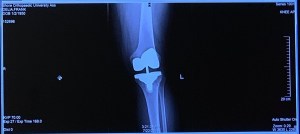

Yesterday was a banner day for my new left knee! First, I was released from PT! Grady, my Physical Therapist, said there was nothing more he could do for me, as he’d given me all the exercises and I was doing them with zero problem! That was nice to hear! An hour later, I had my 5+ week post surgery appointment with Dr Zabinski. I had three X-rays taken, and Dr. Zabinski is thrilled with what he saw, with the way my scar is healing, and with the progress I am making! He even agreed with our time table of having the right knee done when we return from Florida in April! Like I said, a banner day all around!

And what did this all cost, you may wonder. Well, by the time you add up the Hospital Costs, the Doctors’ bills, the cost of Physical Therapy, as well as the cost of everything we had to buy pre-surgery, I wouldn’t be surprised if it’s very close to $100,000. I mean the cost for the actual implant that now lives where formerly my left knee was, cost a whopping $22,028 and the Operating Room for the 2 hours or so it was dedicated to my knee was just over $24,000! Thank God we have great insurance, and in the end, if I’m responsible for anything, it will probably be pennies! Wonder what the Six Million Dollar Man would cost in 2019 dollars??